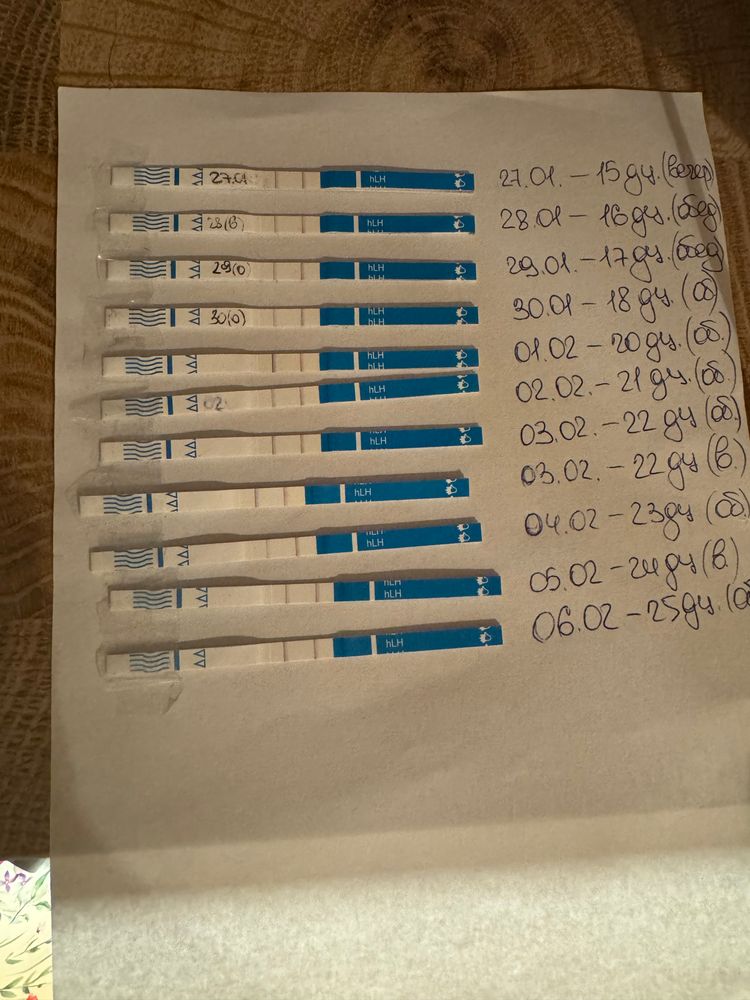

Овуляция была или ещё будет?

Как думаете, овуляция была уже? Если да, то на какой дц?

1 февраля тест положительный,значит была 1-3 февраля

Наталья, а почему тогда не снижается ЛГ, не знаете? На сколько я знаю, то должно снижаться.. вот Фемометр мне показывает сегодня пик🫠

Elena Krushelnytskaya, а от 1 числа что фемометр говорит?там самый яркий тест

Наталья, от первого тоже говорил пик, и тоже 200%🤔

я ради интереса несколько циклов после родов делала тесты на овуляцию, то после пика тесты тускнели.

Наталья, поэтому я и думаю что странный цикл, странные тесты, графики - не перерос ли фоликул в кисту. А то такое ощущение, что овуляция вот-вот наступит и не наступает (по тестах и графику). А вот симптомы все второй фазы (выделения, боль в груди, аппетит, усталость, головная боль)

раньше на 17-19 дц ловила пик